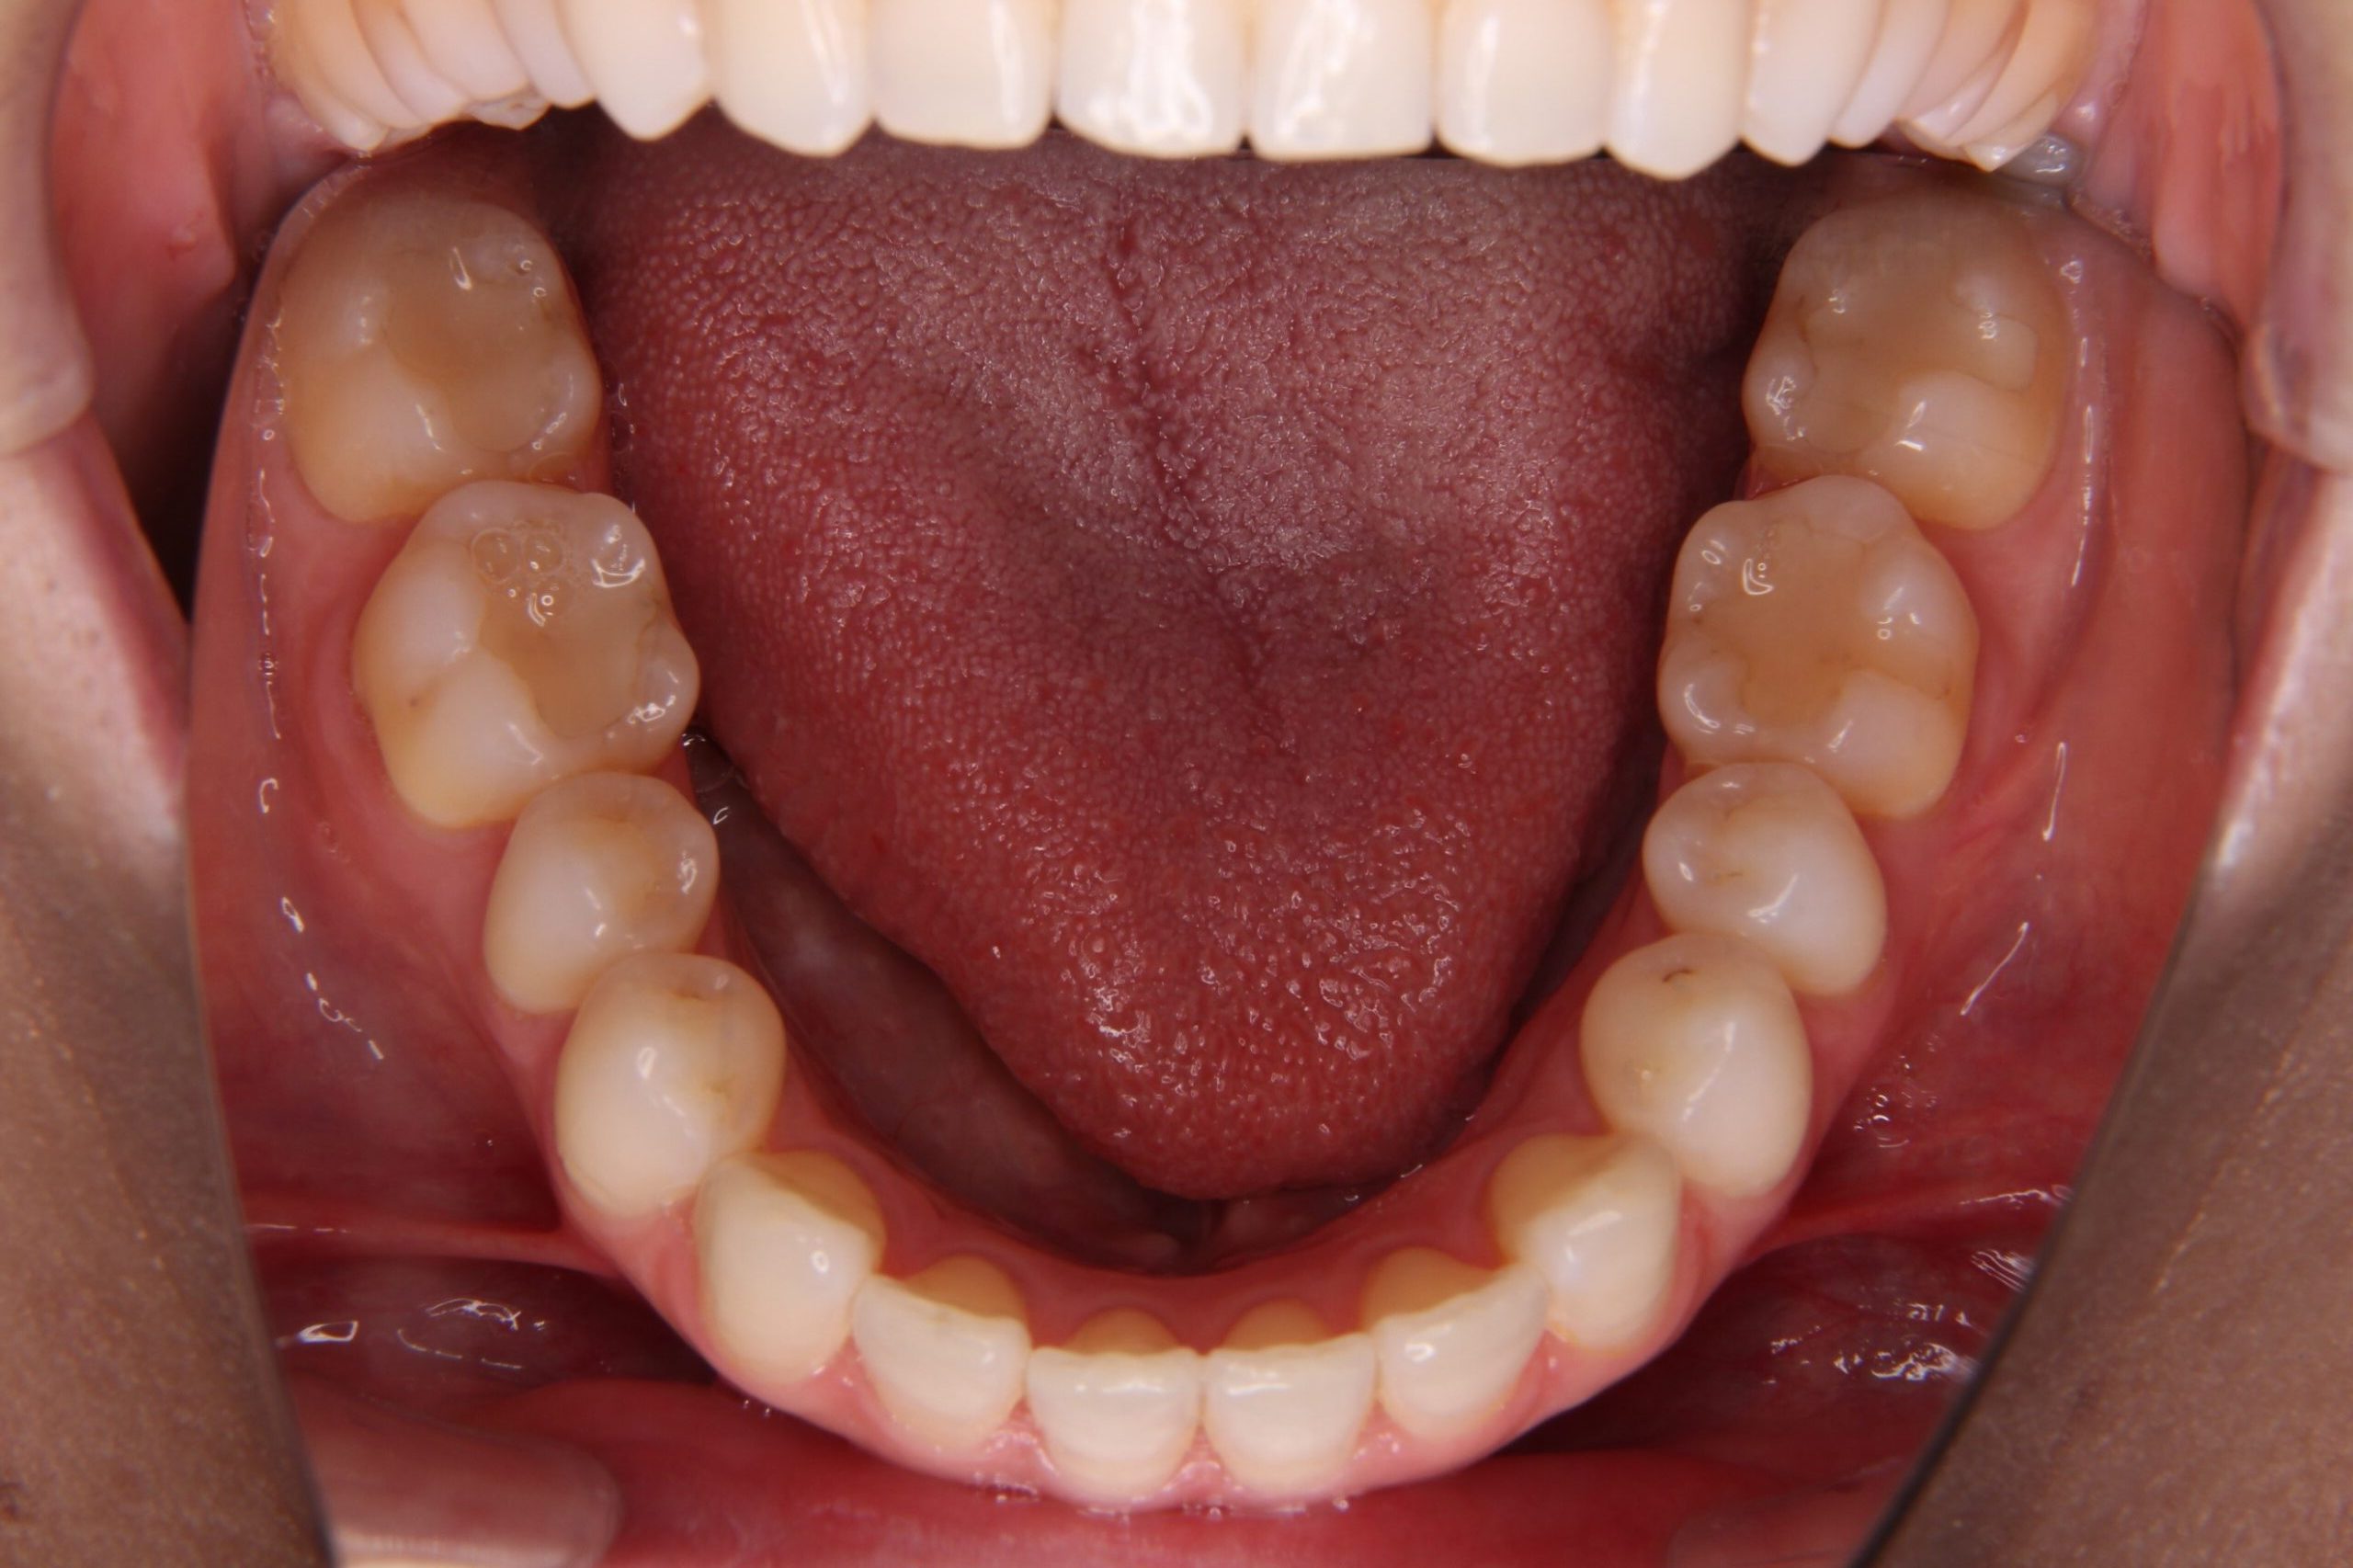

矯正後の歯列

矯正後の歯列がこちらです↓↓↓

私自身、矯正でコンプレックスだった歯並びの改善ができて、本当に良かったと思っています!